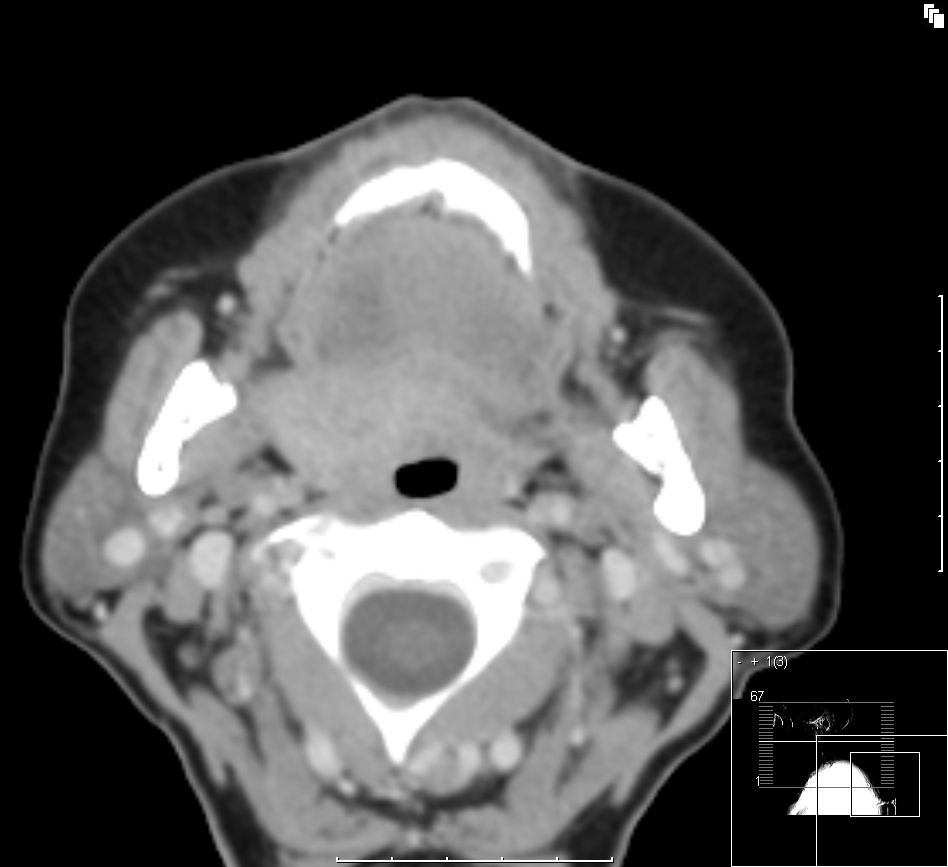

![]() Waldeyer |